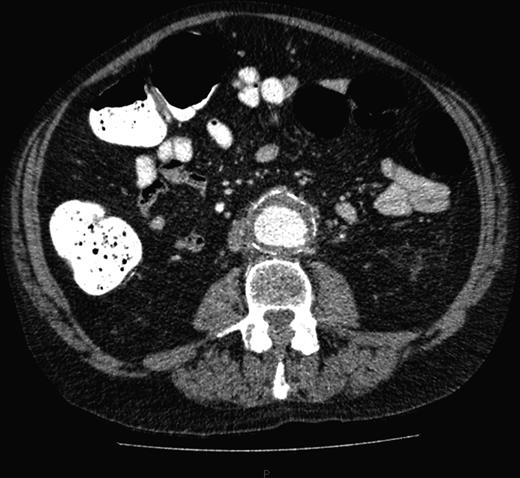

This time he was tachycardic and hypotensive with a much less distended but tender abdomen and still no palpable pulsatile masses. He was clinically stable enough to undergo a further CT scan of the abdomen and pelvis, now revealing a ruptured AAA (Fig. 4). We immediately transferred the patient to the regional hospital where he underwent emergency endovascular aneurysm repair on the same day.

Repeat CT scan of the abdomen, showing evidence of a contained rupture.